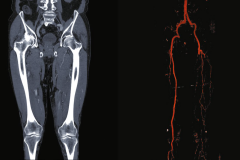

Neurologia to badanie nad sprawnością i wykorzystywaniem kończyny górnej po udarze. Obok wyniki metaanalizy badań o wpływie ćwiczeń na męczliwość i jakość snu u osób z fibromialgią. W Sporcie argumenty za i przeciw podejmowaniu aktywności sportowej po całkowitej wymianie stawu biodrowego. Obok tekst o pracy fizjoterapeuty z piłkarzami - najczęstszych problemach zdrowotnych w tej grupie sportowców i metodach rehabilitacji. W Internie opisujemy chorobę tętnic obwodowych i szczegóły metod jej rozpoznawania u pacjentów gabinetów fizjoterapeutycznych.